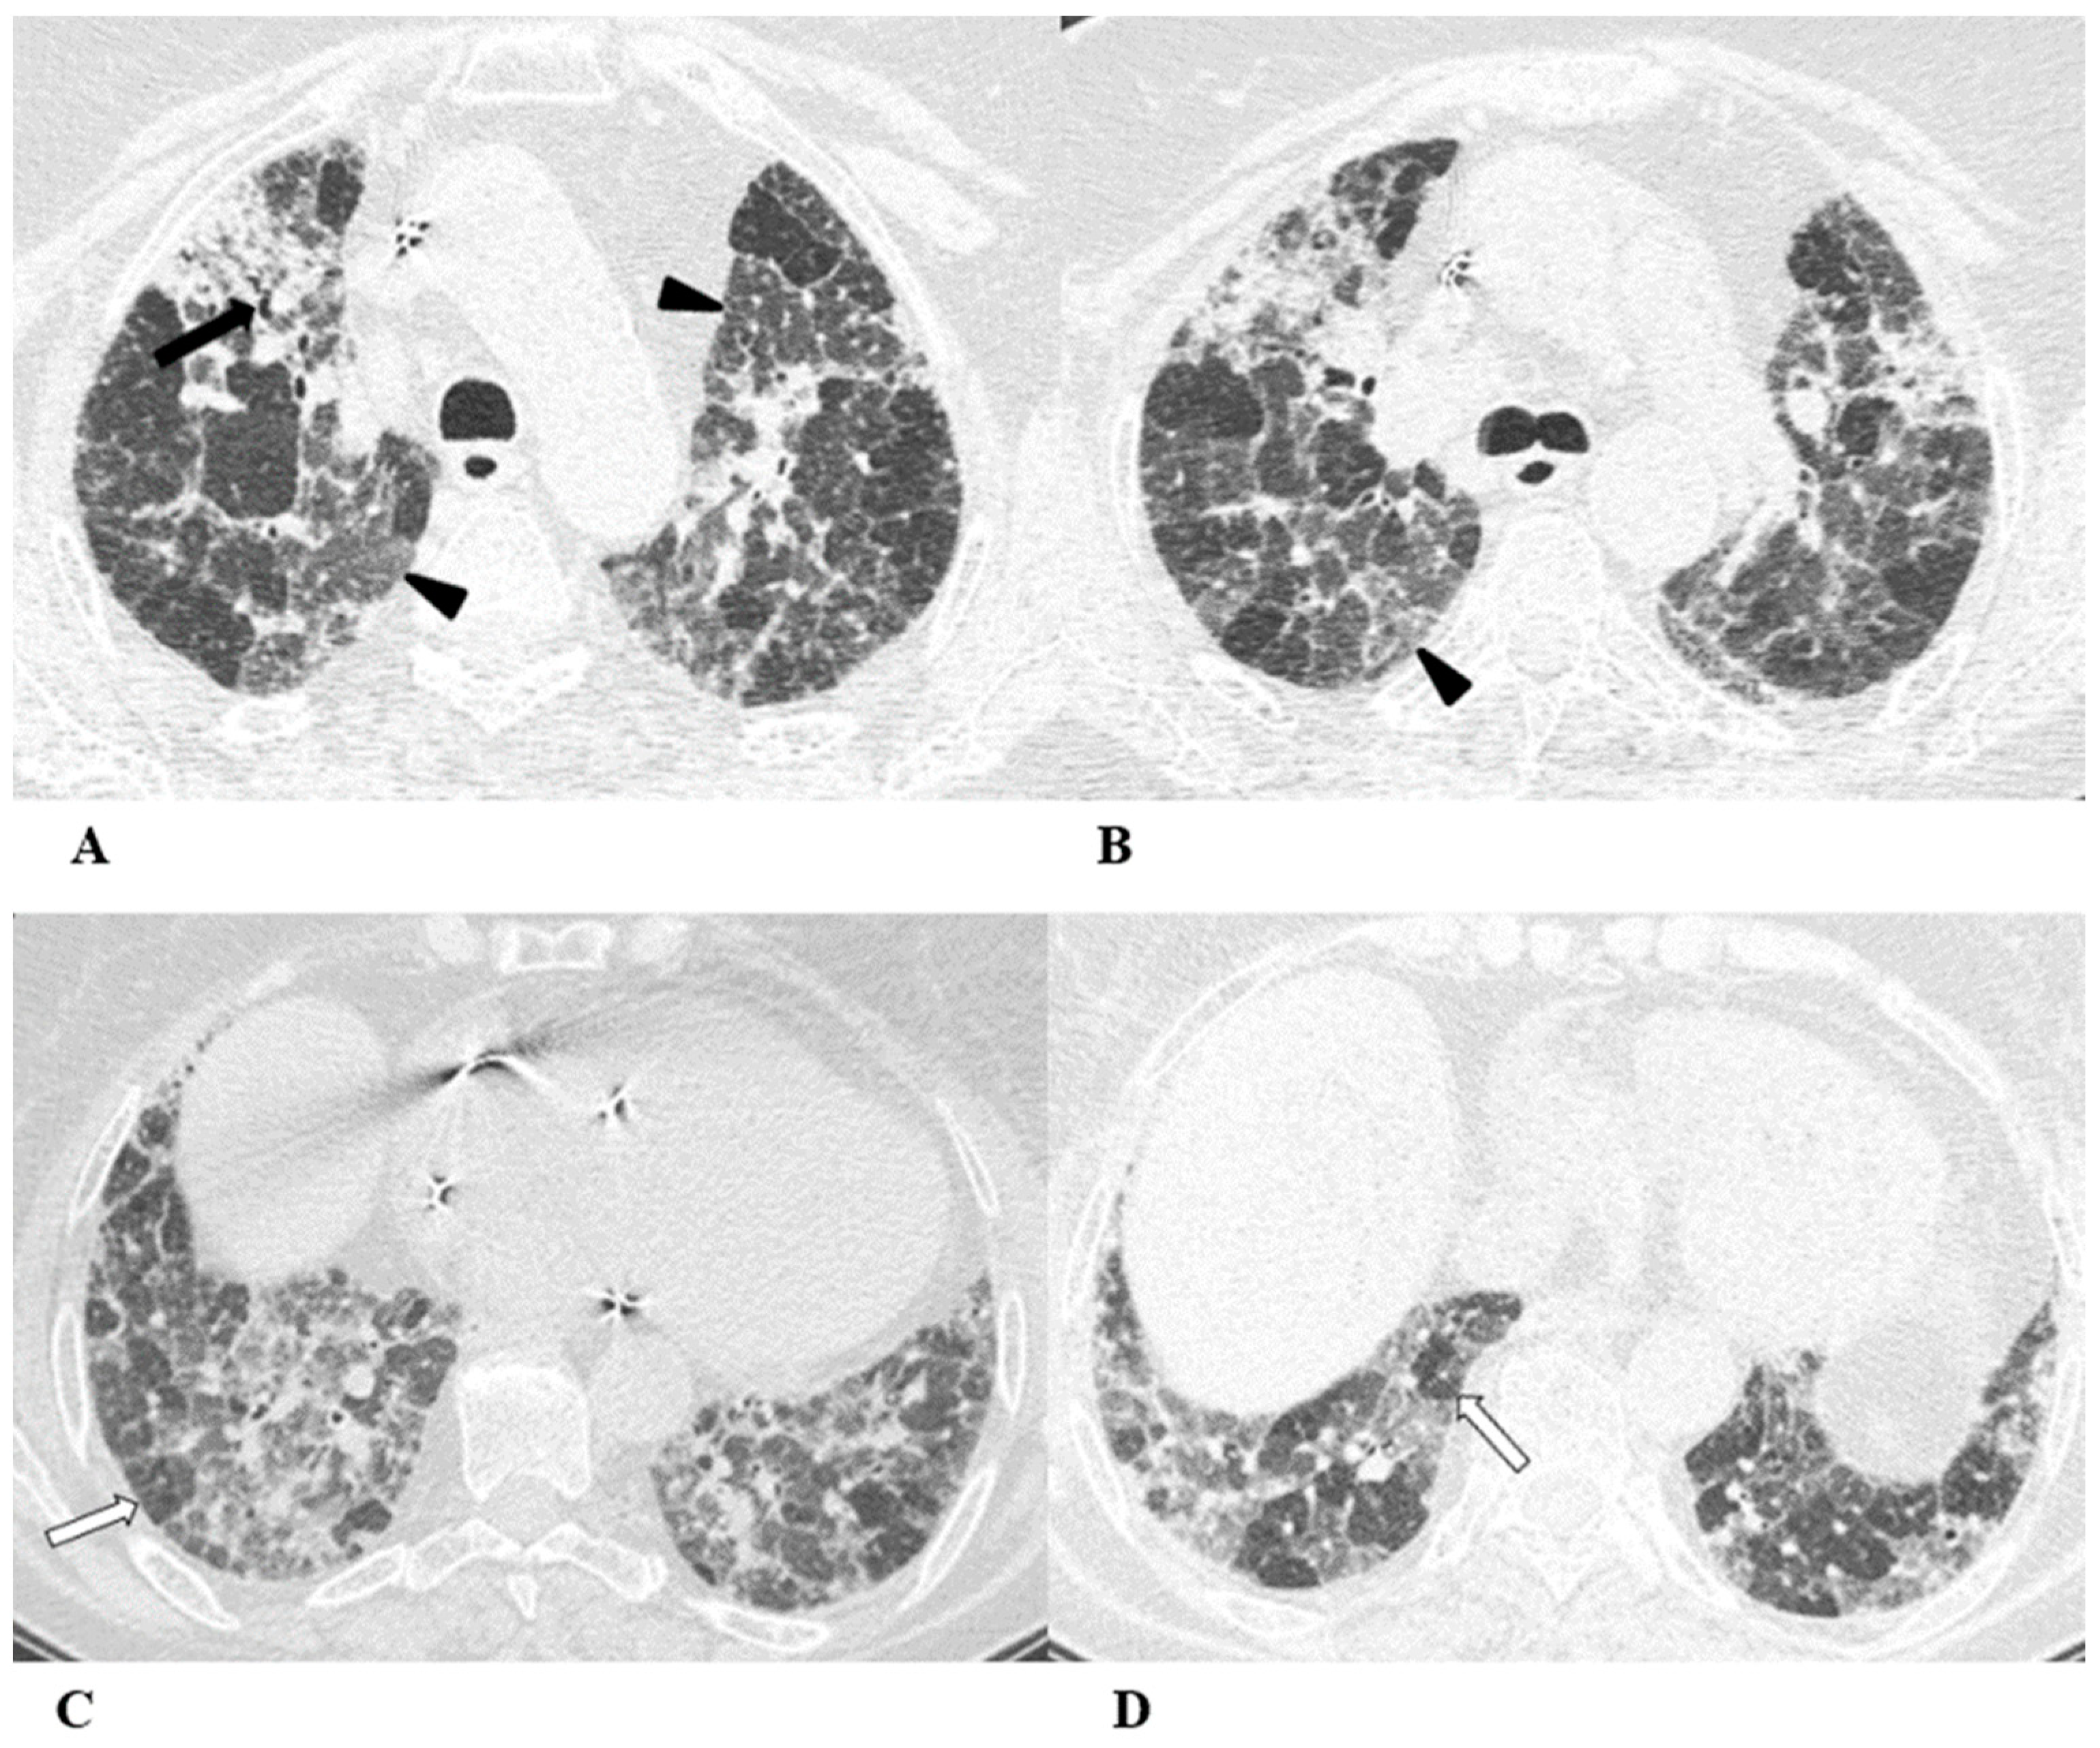

Figure 7.

Sarcoid-like reaction (SLR). A sarcoid-like reaction is a less-common non-pneumonitis irAE determined by the presence of non-caseating granulomatous inflammation in the lung parenchyma and lymph nodes, without criteria for systemic sarcoidosis [21].

Sarcoid-like reaction HRCT findings are represented in most cases by bilateral and symmetrical hilar and mediastinal lymphadenopathy, sometimes associated with peribronchovascular micronodules, peribronchial interstitial thickening and the infrequent coalescence of micronodules forming pseudo-masses with a predominantly dependent distribution. Lung parenchyma may be involved without adenopathy [11,13,22].

Bronchoalveolar lavage (BAL) shows moderate lymphocytic alveolitis, and its first-line treatment is with oral corticosteroids.

(A–D) A 75-year-old man with myelodysplasia and renal cell carcinoma. Fever, fatigue, cough and dyspnea affected the patient from the fifth month of treatment with pembrolizumab.

The axial chest CT image showed widespread micronodules with a miliary and perilymphatic distribution (A). Six days later, along with a moderate clinical worsening, the chest CT highlighted the development of large confluent areas in both lower lobes, with peripheral and declivous locations and the persistence of diffuse bilateral parenchymal micronodules (B); a mediastinal window of the same CT scan of image B demonstrated the volumetric enlargement of some lymphadenopathies in the sub-carinal station (white arrow (C)).

Chest CT performed 20 days later (D) after the discontinuation of pembrolizumab and treatment with oral steroids showed significant improvement in the pulmonary picture, with the complete resolution of the consolidations and a tendency towards the resolution of the bilateral parenchymal micronodulia.